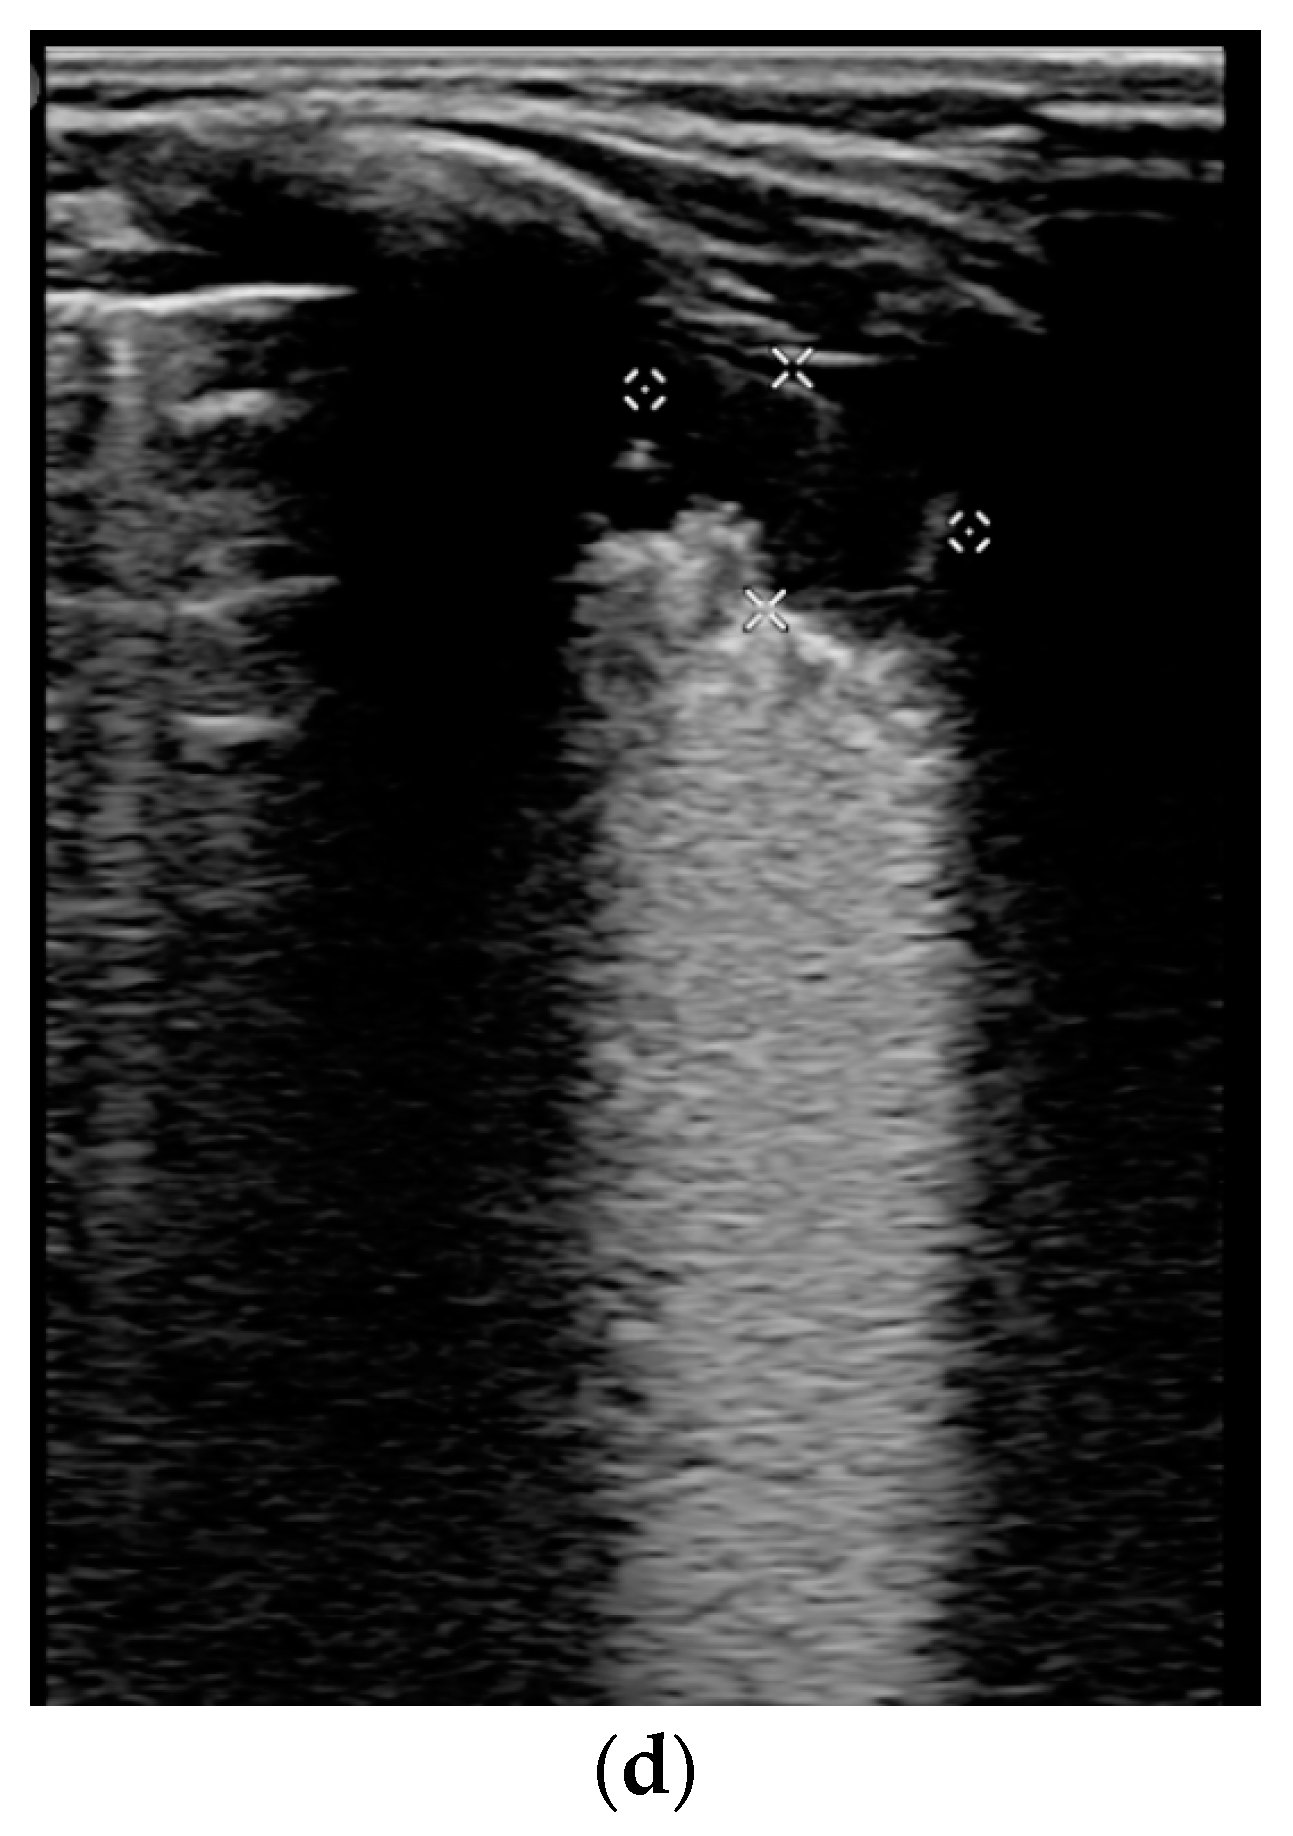

3.3. Lung ultrasound investigation, score and correlation

| LUSS = 0 Points | LUSS = 1 Point | LUSS = 2 Points | LUSS = 3 Points |

| Normal/physiological A-lines | More than 2 B-lines (sparse B-lines) with associated pleural abnormalities | Coalescent or confluent B-lines | Large peripheral consolidation (wider than 1 cm) in association or not with air bronchogram |

| One or two B-lines per intercostal space | ‘White-lung’ aspect or small peripheral consolidation (smaller than 1 cm) |